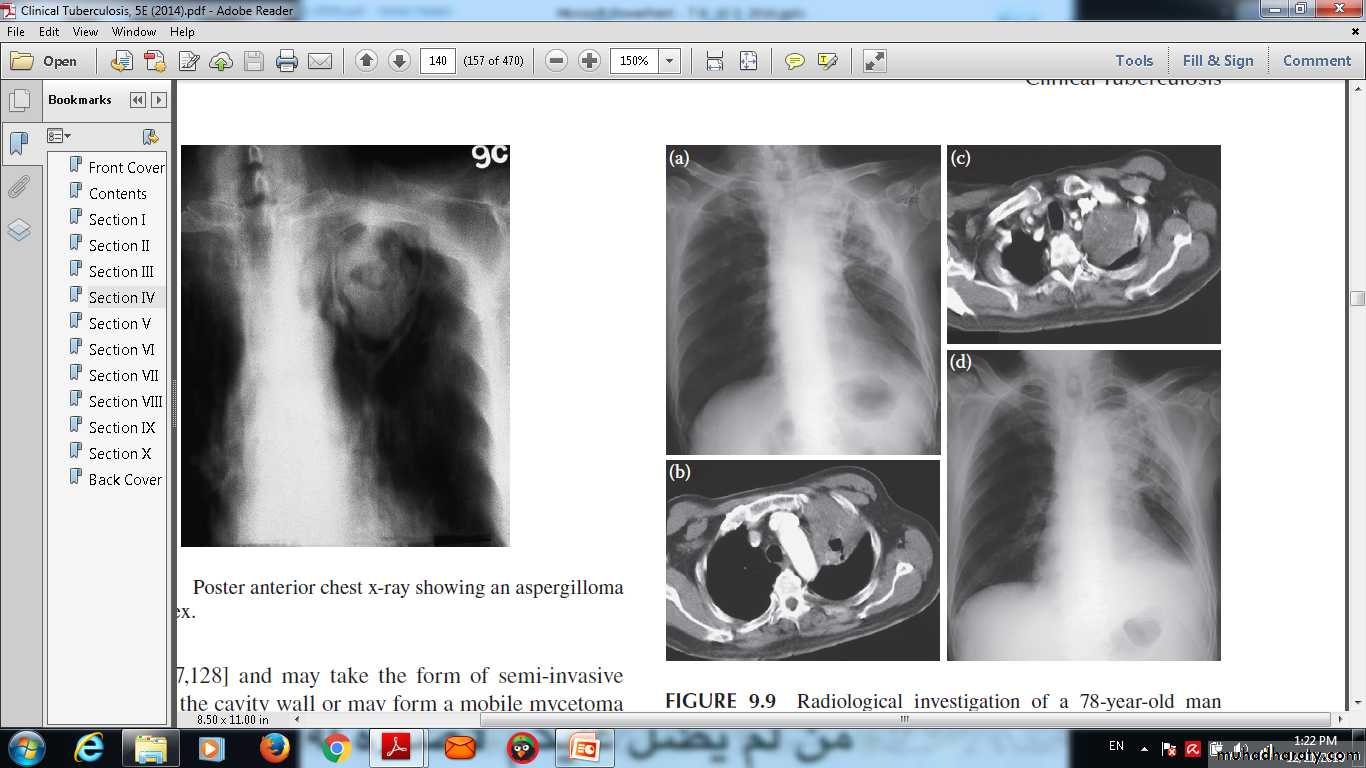

Posteroanterior chest x-ray showing an aspergilloma in the left apex.